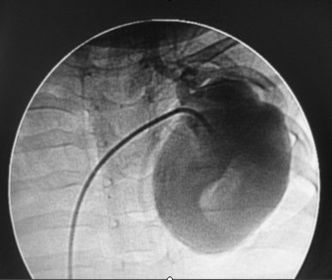

radiografia de contraste se inyecta una solucion de contraste, papilla de bario, se hace un placa y se ve el recorrido , se utiliza en infarto o angina de pecho angiografia coronaria